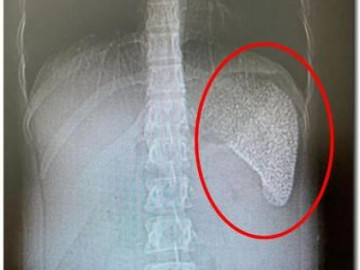

Do người thân thường xuyên bắt được cua núi mang về nấu canh, nhưng nấu chưa kỹ nên bé gái khi ăn phải đã bị sán lá phổi tấn công.